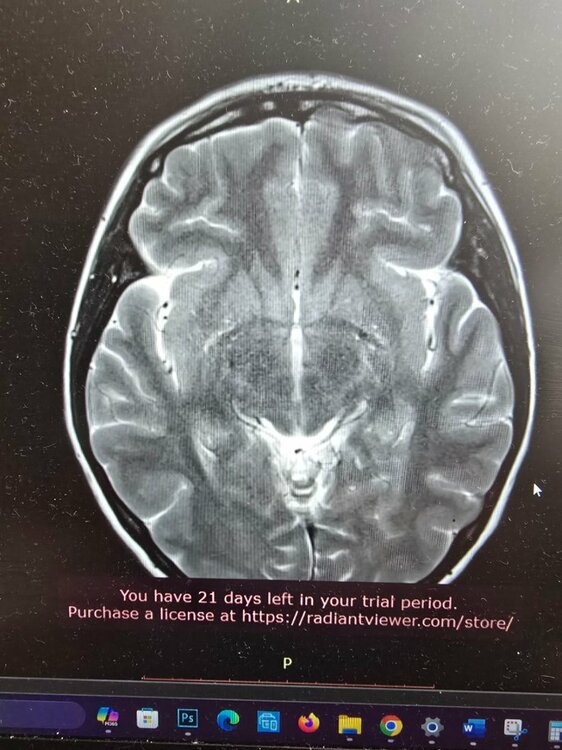

Здравствуйте. Я внимательно посмотрела ваши снимки и описание. Вы уже проделали большую работу — прошли операцию, несколько специалистов и целый комплекс обследований. По МРТ головного и спинного мозга ничего угрожающего нет. Опухолевых или сосудистых изменений не обнаружено. Небольшой «сиринкс» в шейном отделе — это, скорее всего, лёгкое расширение центрального канала спинного мозга. Подобные находки встречаются нередко и чаще всего не несут опасности. Их просто наблюдают раз в год-два, чтобы убедиться, что они не увеличиваются. Поводов для паники нет. Во-вторых, ваши жалобы — чувство «окаменения» головы, боли в шее, тяжесть, головные боли — могут быть связаны с мышечно-тоническим напряжением в шейно-затылочной зоне, которое нередко возникает на фоне остеохондроза, стрессов и гормональных перестроек (в том числе после удаления щитовидной железы). Такие ощущения могут быть очень выраженными и мешать нормальной жизни, хотя причина чаще функциональная, а не структурная. Что сейчас целесообразно сделать: Проверить уровень ТТГ, свободного Т4, кальция и витамина D. После удаления щитовидки важно держать гормональный баланс под контролем. Даже небольшое отклонение может вызывать утомляемость, тревогу, мышечные спазмы и колебания настроения. Сдать ферритин и витамин B12. Дефициты этих веществ часто вызывают слабость, головокружение и ощущение «тумана» в голове. Разобраться с лимфоузлами. Реактивное увеличение до 15 мм на фоне частых воспалений — это чаще следствие хронических очагов (например, миндалин или пазух). Стоит сделать общий анализ крови, С-реактивный белок и обратиться к ЛОР-врачу, чтобы исключить затянувшуюся инфекцию. Для шейного отдела: подойдёт курс мягкой физиотерапии — магнитотерапия, электростимуляция, лечебная гимнастика, релаксирующий массаж. Иногда добавляют препараты с магнием или миорелаксанты, но это решается очно с неврологом. Избегайте агрессивных мануальных воздействий. После операции на щитовидке и при шейных изменениях любые резкие манипуляции противопоказаны. Лучше работать с реабилитологом, который владеет мягкими техниками. Психоэмоциональный компонент. После пережитой операции и постоянных обследований нервная система часто находится в повышенном напряжении. Это естественно. Здесь помогают дыхательные техники, прогулки, нормализация сна и, если необходимо, курс мягких седативных средств по назначению врача. В целом ситуация контролируемая. Сейчас важно не искать у себя опасную болезнь, а постепенно восстанавливать баланс — гормональный, мышечный и эмоциональный. Если хотите, я помогу вам составить поэтапный план восстановления — с обследованиями, питанием, физической активностью и поддерживающими методами. Хотите, чтобы я сделал такой план? ⚠ Важно: Согласно законодательству РФ (ст. 70 Федерального закона № 323-ФЗ «Об основах охраны здоровья граждан в Российской Федерации»), назначение лекарственных препаратов возможно только после очного осмотра врача и установления диагноза. Поэтому приведённые рекомендации не являются индивидуальным назначением, а представляют собой обобщённые терапевтические подходы, применяемые в аналогичных клинических ситуациях. Для точного подбора терапии и исключения противопоказаний необходимо обратиться к врачу очно.

Добрый день всем. Мне 37 лет. 1 года назад удалили щитовидку. По показания (фоликулярный неоплазия, оказалось аденомой). После этого у меня постоянно выполнение лимфатических узлов, и гнойные инфекции они и раньше были.1 недели опухают потом отпускают и опять заново, Я пошла на узи там 2.2см. Отправили к Орл, пока дошла очередь лимфатические узлы уменьшились. Тот отправил делать Мрт. (На Мрт шейного отдела, лимфо узлы 15 млм, и Диски позвонков ранние дегенервтивные изменения, и маленький сиринкс позвонка Т2. Других аномалий не нашли. Головные боли усилилисьи постояннов сердце екала . Я уже к неврологу за таблетки тот прописал успоительные, (то я кажусь ему в стрессе) и отправил меня уже на энцефелограму, там А ритм 8-9 Гц нестабилен, и Интерференция периодических медленных θ -волн без явных очагов. Потом отправил меня к Неурохирургу, тот дал направление на Мрт головы. На мрт головы всё чисто ничего не нашли. У меня голова как будто замороженная, или твердеет окаменеет, даже не знаю как объяснить. Периодически боли с передней шеи где постоянно чувствую там то ли гланды болят какие-то то-ли лимфо...и задняя часть шею болит тоже. Массаж, холодный душ, киропрактик помогает временно. Вес у меня 70кг при росте 159 см. Занимаюсь ходьбой